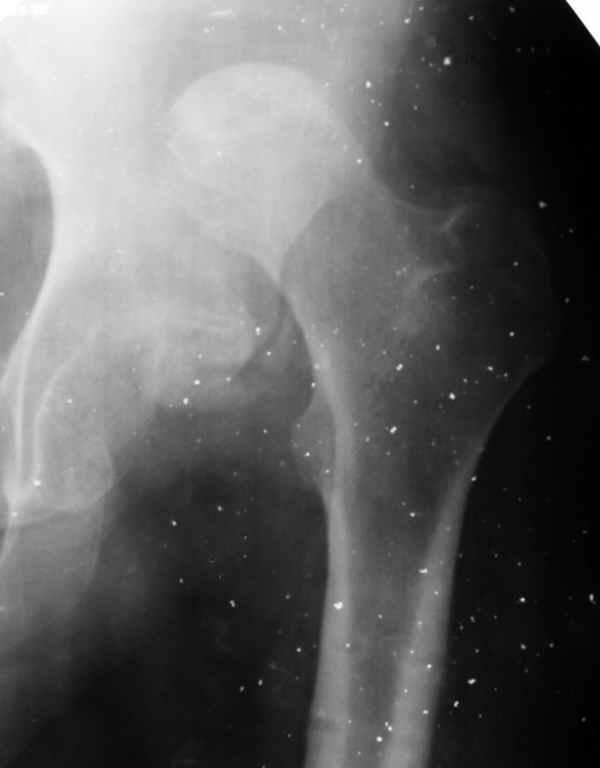

Застарелый вывих бедра (7 мес)

Здравствуйте. К нам поступил мальчик 15 лет с застарелым 7-месячным вывихом бедра из области. Травма мотоциклетная, при поступлении в больницу по месту жительства диагностирован перелом диафиза бедра и не распознан вывих бедра с этой же стороны.

Бедро было синтезировано пластиной и успешно срослось. Как поступить сейчас с вывихом? По КТ видны интерпонированные отломки, впечатление что это фрагменты головки бедра. Поделитесь, пожалуста, опытом. Спасибо.